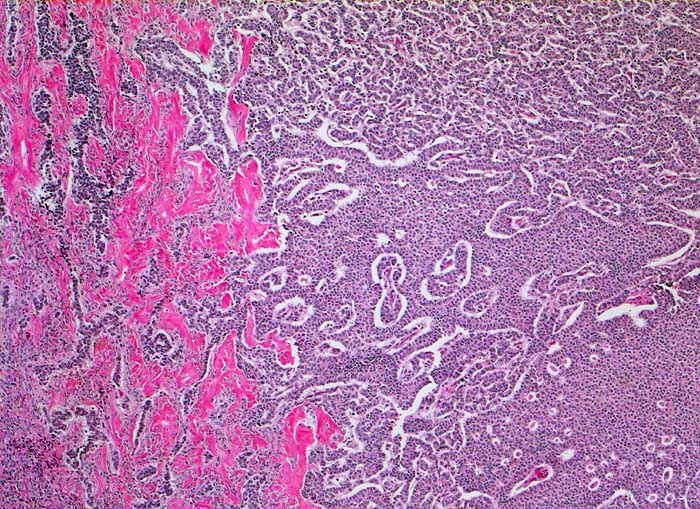

AP/ Granulosazelltumor des Ovars

Granulosazelltumor des Ovars

maligner Tumor

Ovar